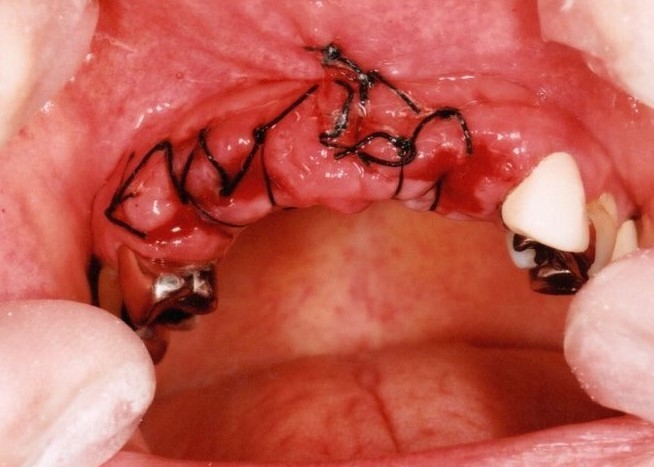

歯周病とインプラント(抜歯即時荷重)<ガイドシステムを使用した埋入法>

インプラント8本で14本の歯を並べたケース・仮歯代含む (函南町在住 女性

抜歯後、片顎8本のインプラントを埋入し、即日に仮歯を製作する事により、1日で片顎14本の歯を回復します。事前にインプラントを埋入する位置をCTによりシミュレーションし、埋入ガイド、仮歯を準備したうえで手術を行います。埋入ガイドにより、正確な位置にインプラントを埋入することができます。

治療の流れ

治療前

下の歯は歯周病でグラグラです。

後のインプラント手術時に、抜歯します。

CT撮影

埋入位置を決めるための装置(ラジオグラフィックガイド)を口腔内に入れCTを撮影します。

埋入ガイド

CT画像上にて決定した埋入位置で製作された埋入ガイド。正確でスムーズな手術を行えます。

仮歯

埋入位置に合わせた仮歯を製作します。

仮歯装着①

インプラント埋入後、その日に用意していた仮歯を装着します。

仮歯装着②

仮歯をネジ止めして固定します。

これはまだネジ穴を塞いでいない状態です。

最終的な被せ物装着

インプラントがしっかり骨に定着したら、型取りをして、最終的な被せ物を製作し、装着します。

完成後のレントゲン写真

最終的な被せ物を装着した状態のレントゲン写真。

(今回は下顎ですが、その前に上顎は治療済みです。)